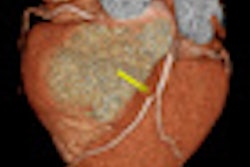

Another Italian CT expert, Dr. Filippo Cademartiri, PhD, from Treviso, made headlines at ECR. He maintained that CT angiography can act as a gatekeeper in coronary artery disease by identifying outlier patients and enabling dedicated trials to characterize biomarkers and genomics of protective/antiprotective factors. To read more, click here.

Meanwhile, cardiac researchers from Barcelona, Spain, revealed that most low-risk asymptomatic patients in their 50s demonstrate occult coronary artery disease at coronary CT angiography, but very few are at imminent risk of death. Click here to learn more.